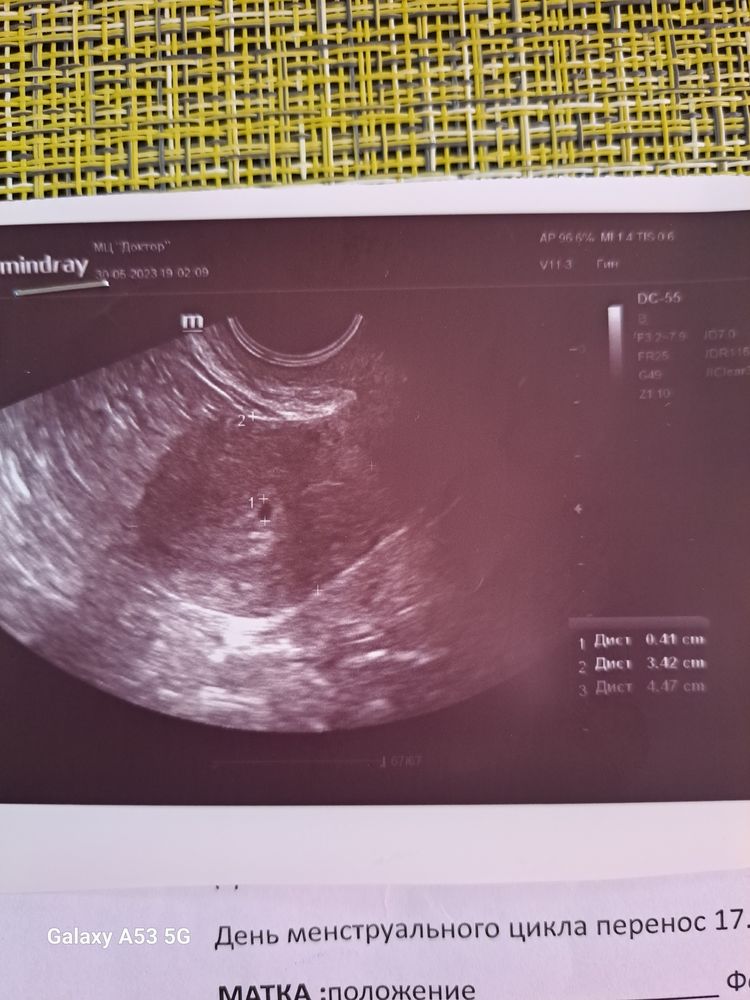

Виктория Хоменкова в ЭКО-мама 3 года 19 дпп... Узи🙏🙏🙏🙏 Я БЕРЕМЕННА ! 19 дпп, сделала, узи... Плодное яйцо в матке, 10 числа сказали приходить, будем слушать сердечко🙏🙏🙏🙏 Посмотрите еще 20 записей на эту тему Отменить Ответить Аля Поздравляю😇🌸рада за Вас! Пусть беременность будет лёгкой и благополучной🙏💯 05.06.2023 Ответить Оксана Поздравляю 🌺🌺🌺 05.06.2023 Ответить Марина Поздравляю Вас❤️❤️❤️ 05.06.2023 Ответить Виктория Хоменкова Марина , спасибо 🙏🙏🙏🙏 05.06.2023 Ответить 32дпп слушали сердечко ❤️ 21 дпп первое узи Чаты Беременных Выберите чат: Январята-2026 Февралята-2026 Мартята-2026 Апрелята-2026 Майчата-2026 Июнята-2026 Июлята-2026 Августята-2026